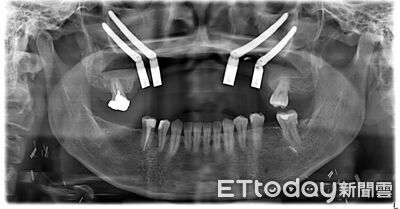

口腔癌長年被視為與抽菸、喝酒、嚼檳榔等習慣高度相關的疾病,但一名40歲的許小姐,生活作息正常且無任何不良習慣,卻在前年確診罹患「上顎牙齦癌」,不僅需大範圍切除上顎骨,還必須拔除鄰近腫瘤的10顆牙齒,身心承受巨大衝擊。 《詳全文...》